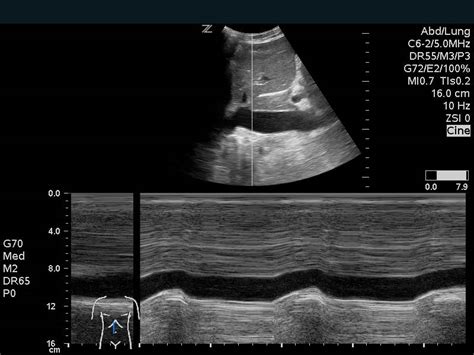

First up, we have Echocardiography . Think of this as an ultrasound of the heart. It uses sound waves to create moving pictures of your heart. It’s non-invasive, meaning there are no needles or anything like that, and it’s super useful for looking at the structure of your heart, how well it’s pumping, and how your valves are working. There are different types of echocardiograms, including transthoracic (where the probe is placed on your chest) and transesophageal (where the probe goes down your throat – a bit more involved, but it gives a clearer picture). Another common type is Electrocardiography (ECG or EKG) is often performed during stress tests to monitor the heart’s electrical activity. This test involves placing electrodes on the patient’s skin to record the heart’s electrical impulses and can provide crucial information on a variety of cardiovascular conditions.

So, what actually happens during a cardiac medical imaging test? The process will vary depending on the type of test, but here’s a general idea of what to expect. When you arrive at the imaging center, you’ll likely be asked to change into a gown. You’ll then be positioned on a table or in a machine, depending on the type of test. A technologist will be there to explain the procedure and answer any questions you have. They’ll also monitor you throughout the test. For some tests, like an echocardiogram, the technologist will place a probe on your chest. This probe emits sound waves that create images of your heart. You’ll likely be asked to lie still and hold your breath for short periods. For other tests, like a Cardiac MRI or CT scan, you might be given an injection of a contrast dye. This dye helps to make the blood vessels and other structures of the heart more visible. You might feel a brief sensation of warmth or a metallic taste in your mouth when the dye is injected. The technologist will monitor you closely during the test to make sure you’re comfortable and that there are no adverse reactions to the dye. The test itself can take anywhere from 30 minutes to a few hours, depending on the type of imaging and the complexity of the study. It’s super important to relax and try to stay still during the test. Movement can blur the images. During the test, the imaging equipment will create a series of images of your heart. These images will then be analyzed by a radiologist or cardiologist, who will look for any abnormalities. Once the test is complete, you’ll be able to get dressed and go home. You might be able to resume your normal activities immediately, or your doctor might give you some specific instructions. If you’ve had a test that involved contrast dye, you’ll likely be advised to drink plenty of fluids to help flush the dye from your system. It’s a pretty straightforward process, and the technologists are usually very experienced and helpful. They’ll make sure you’re comfortable and answer any questions you have along the way. Your doctor will discuss the results with you and let you know if any further steps are needed.